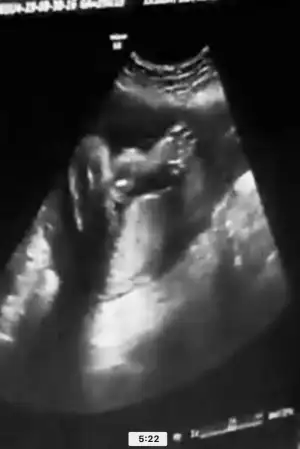

Eki Görüntüle 2547536 Eki Görüntüle 2547537